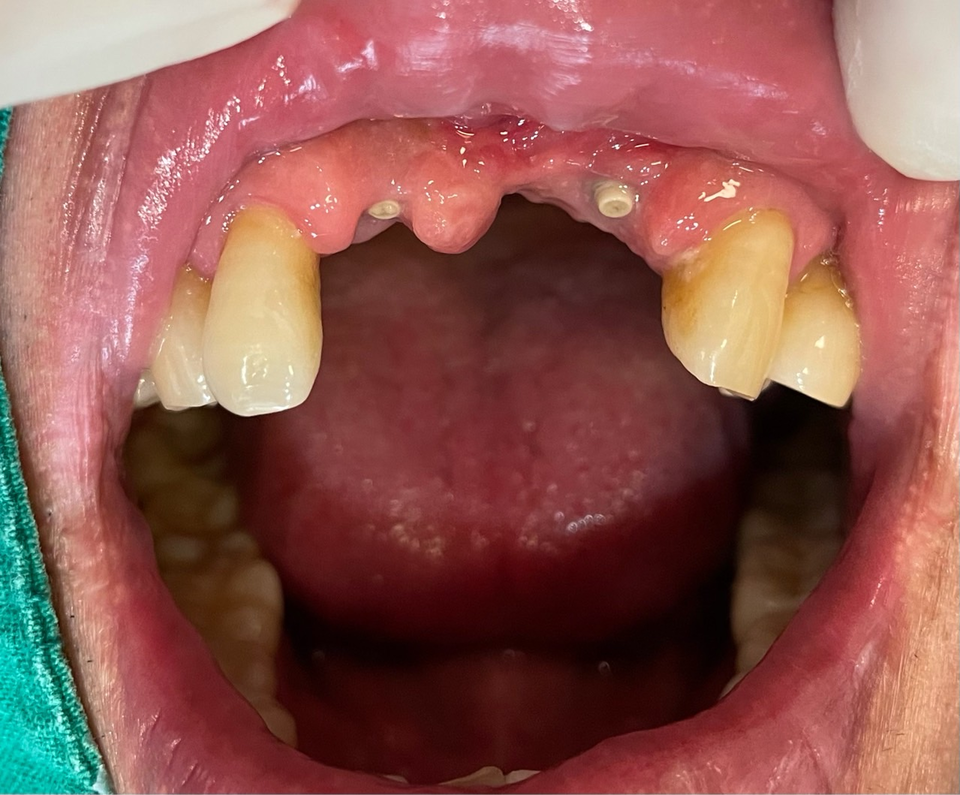

Bright implant tissue Level은 Dentium Simple Line과 비슷하며 tissue level 상부 돌출부는 6각으로 되어 있다. 베벨까지 내려가서 측방압에 강하고 실링효과가 높아 leakage 없고 따라 bone loss의 염려가 없다.

또한 internal 방식의 bone level과 tissue level의 external 방식 2종류로 구성되어 있고, 변환 abutment를 꽂으면 bone level이 tissue level로 변신한다. 그러면 디지털 보철 제작이 더욱 쉬운 형태로 바뀐다.

물론 개인적으로 3 piece 보다 2 piece가 나을 것 같기에 필자는 tissue level을 선호한다. 이렇게 internal을 external 방식으로 변환하는 이유는 디지털 스캔, Hexa 체결의 안착을 더욱 정확히 확인할 수 있기 때문이다.

또한 착탈이 가능한 스크류 방식의 보철로 제작하는데 fixture 식립각도의 차이에도 장착이 쉬운 외부 Hexa가 절대적으로 유리하기 때문이다. 또한 교합이 낮아지는 sink down 염려도 거의 없다.

재미난 건 식립 후 머리꼭지가 보인다는 것이다.

사과 꼭지 같은 게 커버스크류이다. 심고 나면 미소가 나오는 이유이다.